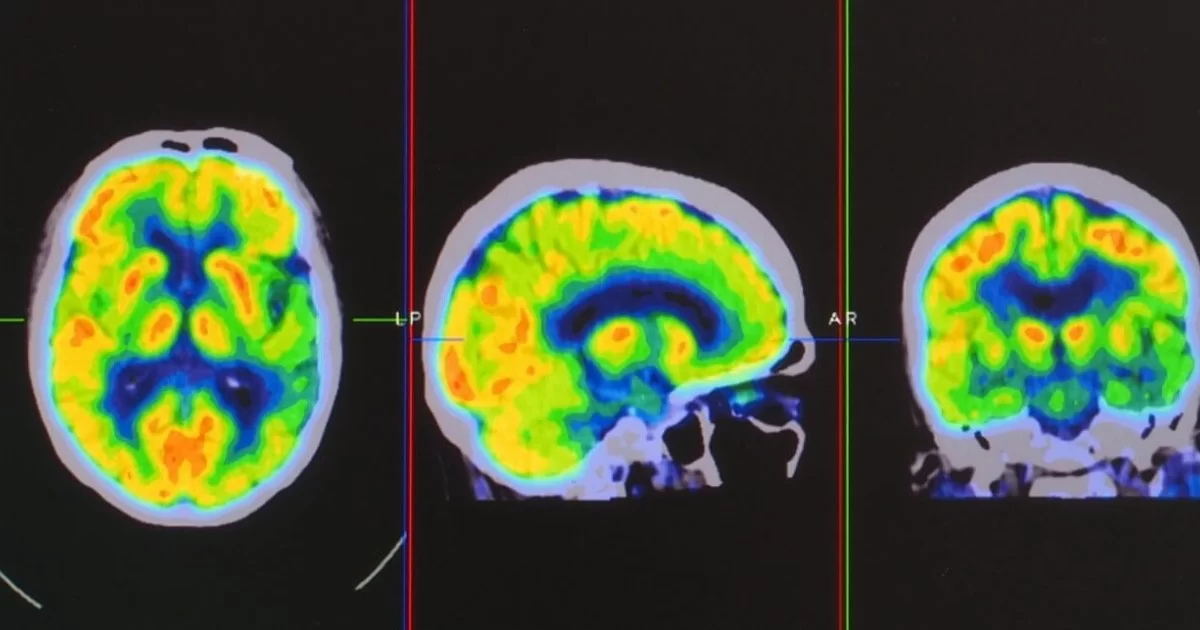

O PET-CT Neurológico é uma técnica de imagem avançada que combina a tomografia por emissão de pósitrons (PET) com a tomografia computadorizada (CT) para fornecer uma visão detalhada do cérebro e do sistema nervoso central. Este exame é utilizado para avaliar uma variedade de condições neurológicas e psiquiátricas.

O PET-CT Neurológico é uma combinação das tecnologias PET e CT, proporcionando uma análise detalhada da atividade metabólica e da estrutura do cérebro. O PET usa um traçador radioativo para visualizar a atividade metabólica cerebral, enquanto o CT oferece imagens anatômicas detalhadas.

- Tomografia por Emissão de Pósitrons (PET): O paciente é posicionado em uma máquina PET que detecta a radiação emitida pelo traçador. As imagens PET mostram a atividade metabólica cerebral.

- Tomografia Computadorizada (CT): Imagens CT são obtidas para fornecer informações anatômicas detalhadas do cérebro, que são combinadas com as imagens PET para uma avaliação completa.

- Análise dos Resultados: As imagens PET-CT são avaliadas por um radiologista especializado, que interpreta a atividade metabólica e as estruturas cerebrais para identificar anomalias.